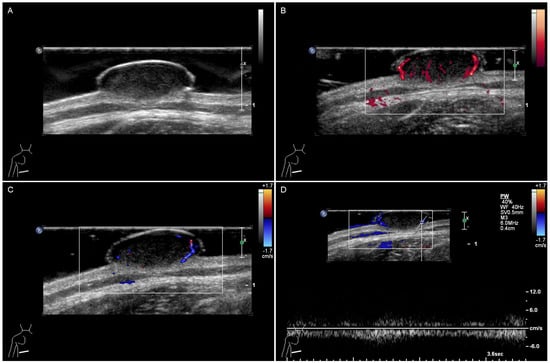

Objectives: To strengthen the recognition of juvenile xanthogranuloma (JXG) by analyzing ultrasound findings. Methods: This study retrospectively enrolled these patients with pathologically confirmed JXG from January 2011 to March 2025. The clinical, imaging, pathological features, and prognosis of all included patients were analyzed. [...] Read more.

Objectives: To strengthen the recognition of juvenile xanthogranuloma (JXG) by analyzing ultrasound findings. Methods: This study retrospectively enrolled these patients with pathologically confirmed JXG from January 2011 to March 2025. The clinical, imaging, pathological features, and prognosis of all included patients were analyzed. All the imaging features were evaluated in consensus by two radiologists. Results: Fourteen patients were included in the study. A total of 78.6% presented with solitary masses. The age of the patients ranged from 2 months to 48 years. Those aged ≤1 year accounted for 64.3% of the sample. The lesions were predominantly located on the head and face, and the skin of most patients was yellowish-orange. The ultrasound manifestations are mostly hypoechoic masses with clear boundaries and regular shapes. Contrast-enhanced ultrasound shows a slight homogeneous enhancement, and on shear wave elastography, it appears to be relatively hard. Conclusions: JXGs are more common in infants or young children and present with yellowish-orange, cutaneous lesions. Ultrasound revealed homogeneous, well-circumscribed, regular hypoechoic nodules. Multimodal imaging may be helpful for preoperative diagnosis. Full article

Figure 1